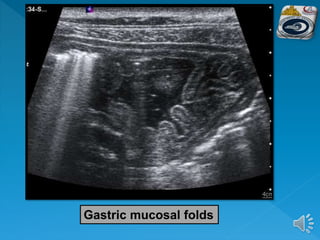

 In a non-distended condition the mucosal folds

of the gastric corpus and fundus are well

demonstrable

Gastric mucosal folds

 The muscularlayer of the stomach, especially that of the antrum, is more pronounced than in other parts of the intestine.  In a non-distended condition the mucosal folds of the gastric corpus and fundus are well demonstrable